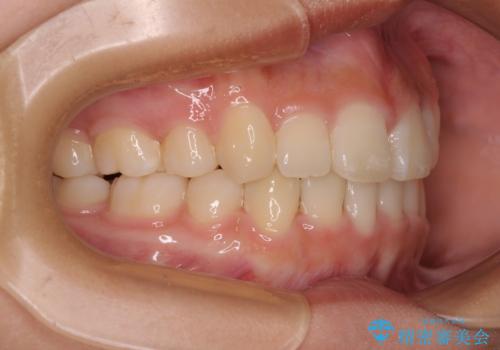

上顎骨幅が狭い 急速拡大装置を併用した抜歯矯正

- 歯列全体の叢生を気にして来院された患者様です。

検査を行った結果、上顎骨の横幅が相対的に狭いことが分かり、叢生が強いことから、急速拡大装置にて上顎骨を側方に拡大することで、叢生の解消と奥歯の咬み合わせ改善を図ることとしました。

一般的には上下左右の第一小臼歯4本を抜歯する必要がありますが、拡大量によっては非抜歯矯正の適用となる可能性があるため、まずは非抜歯矯正で治療を開始し、抜歯が必要と判断された時点で速やかに4本抜歯を行うこととしました。